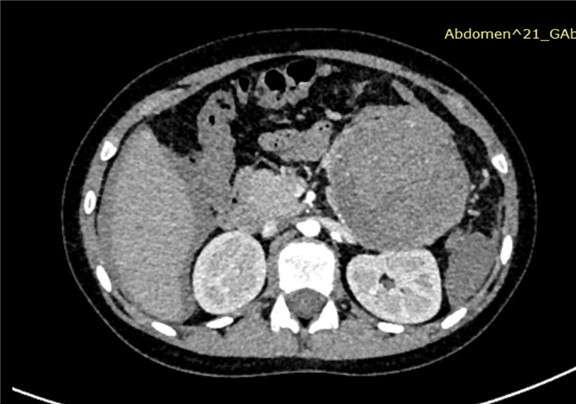

上腹部增强CT:胰尾部占位性病变,考虑胰腺尾部肿瘤并破裂出血,以胰母细胞瘤可能性大,不除外胰腺实性假乳头状瘤,肝周积液、积血,符合肿瘤破裂所致。

术前CT检查:

动脉期

静脉期